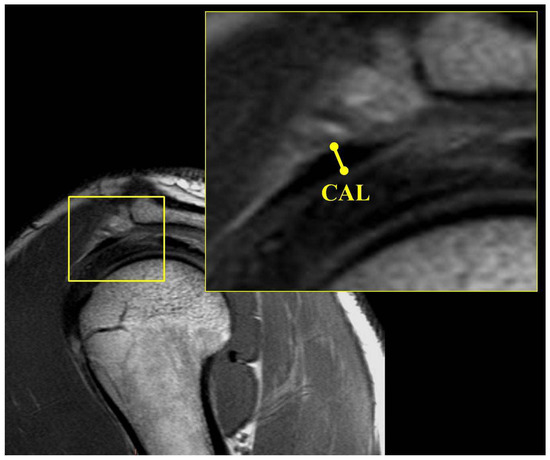

| Sag CAL thickness | 1.78 ± 0.66 (0.8–4.1) | 1.92 ± 0.69 (0.9–3.7) | 2.03 ± 0.75 (0.9–4.6) | 0.224 | 0.053 | 0.389 |